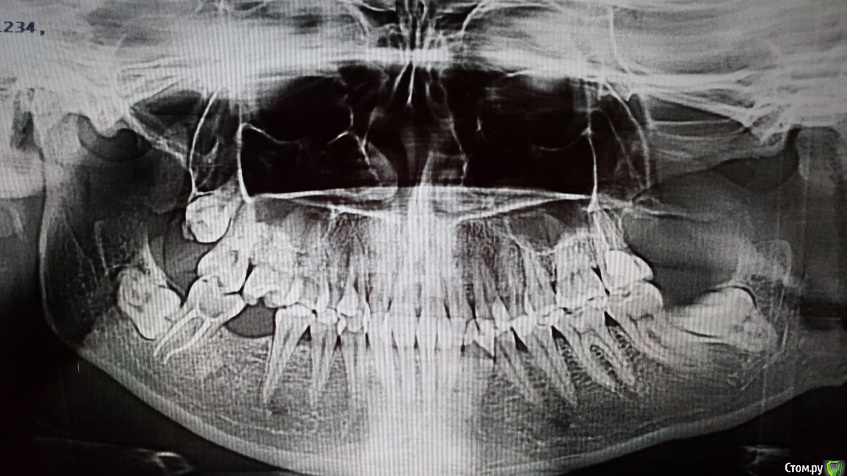

Tesh Опубликовано 21 сентября, 2018 Поделиться Опубликовано 21 сентября, 2018 (изменено) Доброго времени суток! Столкнулась с такой проблемой: В конце июля этого года, находясь в другом городе, заболела острым фарингитом. Через два дня, во время вечерней чистки зубов, появился гнилостный запах и кровь со стороны зубов верхней челюсти слева (5-6-7 зубы), после чего начались ноющие боли и сладкий привкус во рту вытекающей жидкости из данной области (предположила, что гной). После посещения стоматологии, на следующий день, врачи не нашли проблем со стороны данных зубов и предположили гайморит. В течении последующих двух недель, мне исключили (по ренг. снимку) гайморит и посоветовали идти к стоматологу, который в свою очередь также не нашел видимых причин моих проблем, но предположил, что дело в дистопированноми и ретенированном зубе мудрости, после чего его удалил (резал десну, пилил кость). Заживление проходило быстро, принимала антибиотики и делала ванночки. На 5-й день после удаления снова появились ноющие ощущения. С момента удаления прошел месяц, после этого у меня усилились ноющие боли в стороне тех зубов, появилось чувство давления при наклоне головы вперед-назад, и появилось чувство жжения в тканях чуть выше места удаления, все так же чего-то текло со стороны тех зубов и все это дело сопровождается температурой тела 37.1 в среднем. Со всей этой историей я обращалась к хирургу, который удалял зуб, в челюстно-лицевой госпиталь и в одну клинику. Но врачи не могут установить точную причину подобного дискомфорта. Хирург предположил пульпит 6ки и невралгию тройничного нерва, а челюстно-лицевой и клиника: процесс заживление костной ткани после удаления. В клинике также уточнили, что если не пройдет спустя 3-4 месяца следует делать пластику гайморовых пазух (Оо). Сейчас ничего не течет, но так же ноет. Больше беспокоит вопрос, а что если идет воспалительный процесс и чем дольше я жду, тем.. и думать страшно. Чего делать-та? Изменено 21 сентября, 2018 пользователем Tesh Ссылка на комментарий

DmitrySH Опубликовано 13 декабря, 2018 Поделиться Опубликовано 13 декабря, 2018 1. На КТ надо нормально посмотреть зуб 27. По этим снимкам мне он не очень нравится2. Убрать 38 Ссылка на комментарий